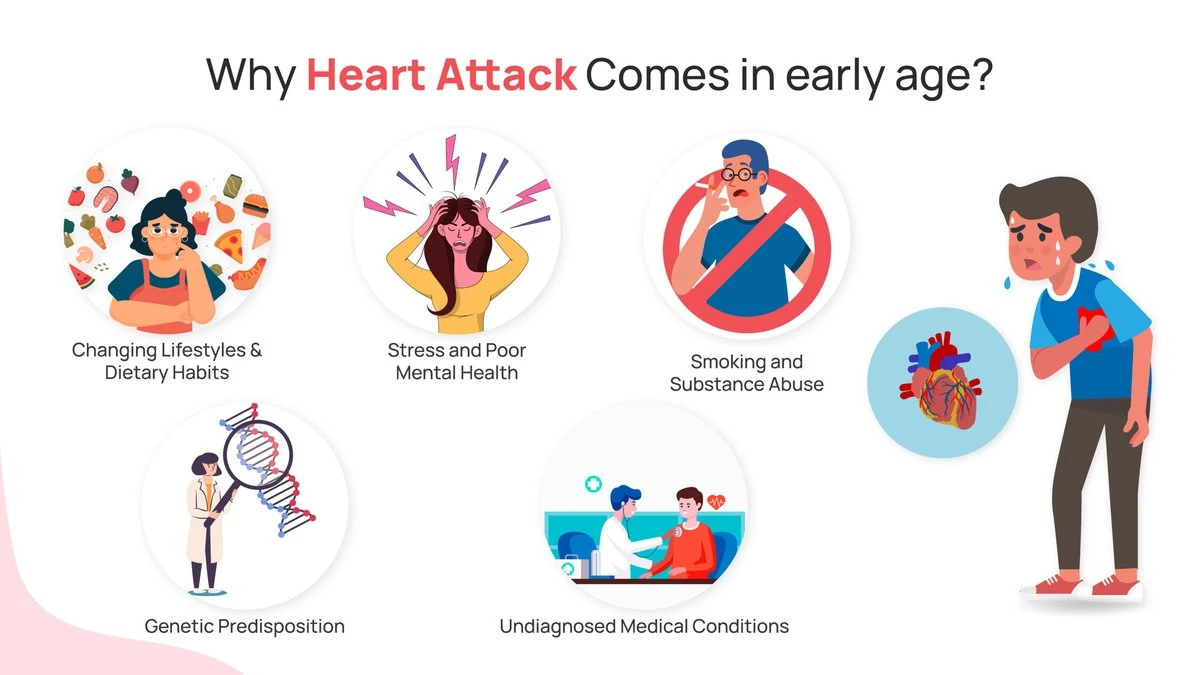

Máte pocit, že se vás kardiologická ambulance týká až v důchodu? Nová data z českých nemocnic za únor 2026 ukazují, že počet mladých pacientů s akutním selháním srdce vzrostl o 14 %. Nejde o náhodu, ale o důsledek specifických návyků, které považujeme za normální, ale naše tepny je vnímají jako rozsudek. Možná právě teď děláte jednu z věcí, která tvoří neviditelnou sraženinu, a přitom řešení máte přímo pod nosem.

Zatímco klasické cigarety jsou na ústupu, nastoupil nový trend. V únoru 2026 vidíme v českých ulicích masivní nárůst používání elektronických cigaret a pití energetických drinků s extrémním obsahem kofeinu a taurinu. Pro mladé srdce je to jako neustálé bičování unaveného koně.

Kombinace nikotinu (který stahuje cévy) a vysokých dávek stimulantů (které nutí srdce pumpovat rychleji) může vyvolat takzvaný koronární spazmus. Jde o situaci, kdy se zdravá tepna náhle stáhne a nepustí krev dál. Výsledkem je infarkt u člověka, který má cévy jinak úplně čisté.

4. Chronický stres a „nedostatek spánku jako status“

V české korporátní kultuře je stále moderní chlubit se tím, že spím jen 5 hodin. „Doženu to o víkendu,“ říkáte si možná. Jenže spánkový deficit se nedá splatit jako hypotéka. Při nedostatku spánku tělo produkuje nadbytek kortizolu a adrenalinu.

Tyto hormony udržují vaše cévy v permanentním napětí. Pokud spíte méně než 6 hodin denně po dobu delší než jeden měsíc, riziko kalcifikace (vápenatění) tepen se zvyšuje o 27 %. V kombinaci s českým stresem z cen energií a bydlení, který je v roce 2026 stále aktuální, jde o toxickou směs.